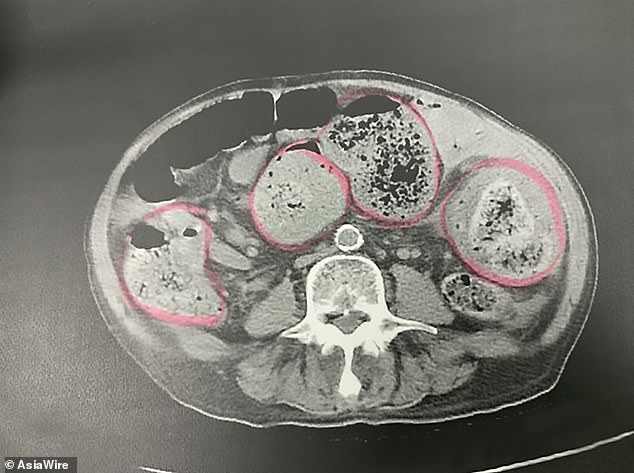

As soon as doctors learned the facts of his situation, they performed a scan of his midsection and found something alarming. There was a nearly 15-inch brick of hardened feces blocking his digestive tract.

Because the man was at risk of “exploding” because of the fecal hockey puck, they decided to put him into emergency surgery. However, the doctors at the Kaohsiung facility had their work cut out for them because they needed to remove a foot-long section of the elderly man’s bowel in order to get the solidified blockage out of his body.